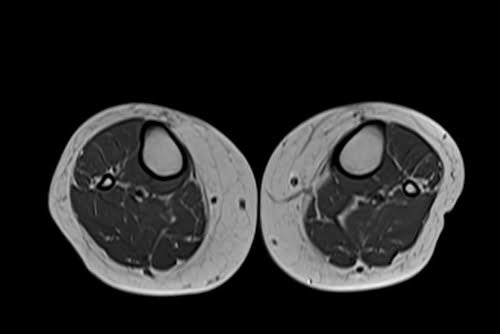

mri lower legs (calves) t1 axial image 2 - MRI